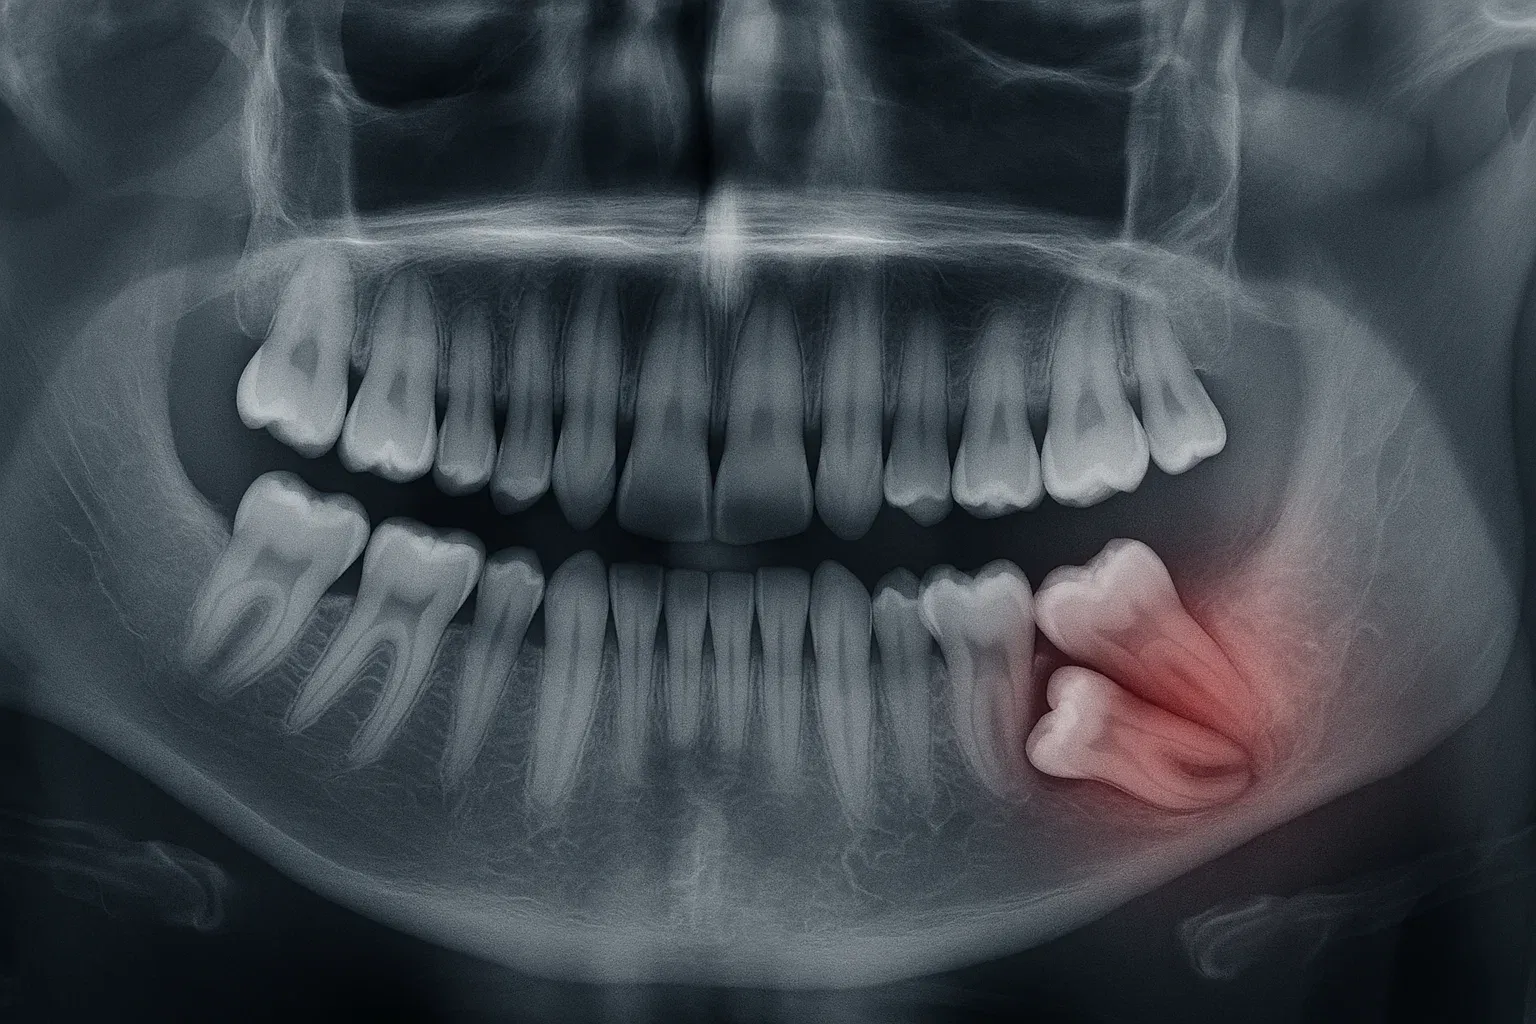

Dişin konumu, açısı ve çevre dokularla ilişkisi kolayca görülür.

Radyolojik incelemelerde gömülü dişler farklı pozisyonlarda olabilir:

Çoğu zaman röntgende görülür. Açısı yatay, eğimli veya dik olabilir. Bazen yalnızca ufak bir kısmı ağız içinde görünür.